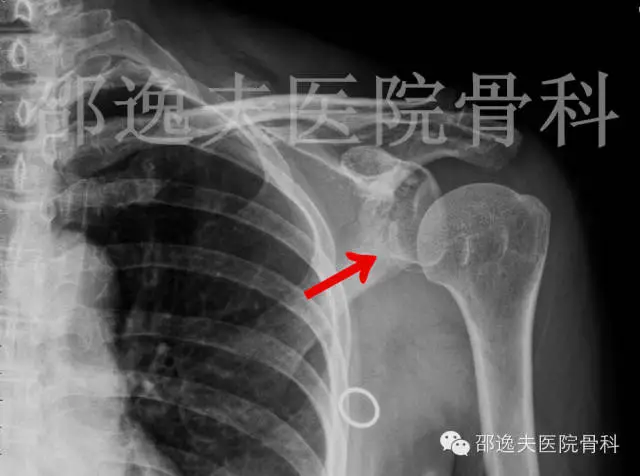

手法复位后X线片

肩部CT扫描

这是典型的骨性Bankart损伤,即指外伤导致肩关节前脱位后与肩关节盂前下缘撞击发生的关节盂前缘撕脱骨折。